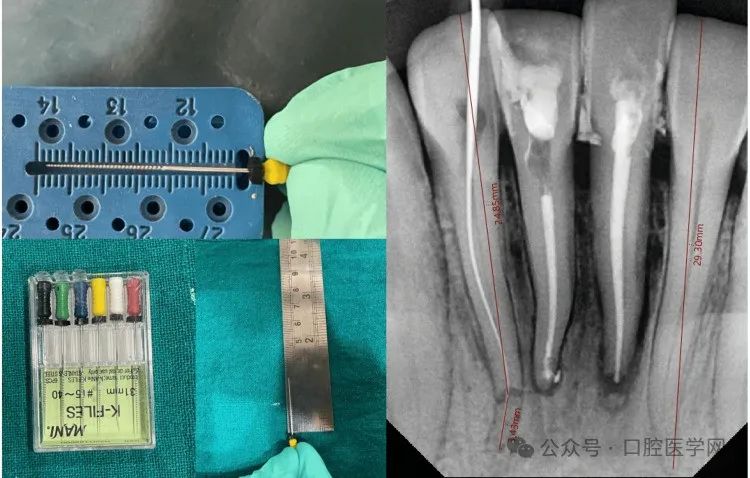

第二种方法采用非手术方式对42号牙冠方与根尖断端进行对位。最初对42号牙采取观察策略,但因患者主诉不适、疼痛及牙齿松动加重,决定实施非手术根管治疗重新连接冠方断端。遵循COVID-19防护措施、患者知情同意及防护技术。对患者实施麻醉,橡皮障隔离。制备髓腔入口,去除冠方断端牙髓。使用25毫米K锉在冠方断端建立初步疏通及滑行通路。冠方断端疏通及预备采用K锉配合电动马达手机振荡头(NSK)。首先仅预备冠方断端,建立直线通路,放置氢氧化钙封药。保留弯曲的根尖断端。三天后患者根管疼痛复发,药物治疗无效。再次检查放射片,推测根尖三分之一断端残留牙髓可能是疼痛持续原因。使用31毫米锉疏通根尖断端,采用直线通路进入牙根冠方至根尖断端。采用平衡力技术冠向下预备确保成形。通过根尖定位仪及影像学分析确定工作长度,使用根管测量尺测量。该牙工作长度约28.30毫米(图6)。

根管扩大使用10K、15K、20K、25K、35K系列K锉。操作时使用振荡头配合Endomate DT电动马达,所有锉转速40,扭矩0。每支锉使用后进行EDTA润滑、2.5%次氯酸钠及生理盐水冲洗。使用牙胶尖和AH Plus封闭剂进行充填。采用热垂直加压技术使用阻塞笔操作。最终使用GIC完成根管治疗后修复(图7)。